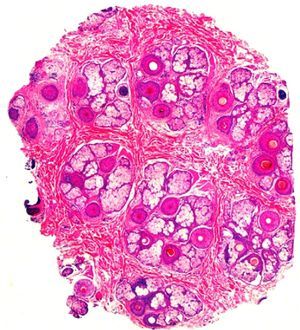

Histopathology showed in all cases preserved number of follicular units at the isthmus level and preserved follicular density (Fig. 3). There was an increased number of follicles in catagen/telogen phase and decreased number in anagen. On the average 33% were in telogen versus 67% in anagen which is a sign of shortened hair cycle and premature conversion to catagen. Pigment casts were observed in a few follicles as a result from abrupt transition of anagen into catagen. At the infundibular level some follicles showed dilated empty infundibular ostia filled with sebum and keratin, which corresponds to the yellow dots on dermoscopy. A prominent feature was the presence of dense inflammatory infiltrate at the level of the isthmus around the follicles and interstitial in the interfollicular deep reticular dermis. The infiltrate was composed of neutrophils, lymphocytes, histiocytes and many plasma cells as well as red blood cell extravasation. Another feature was the increased number of fibrovascular streamers (stelae) showing inflammatory cells (lymphoctyes and plasma cells) and dilated vessels.